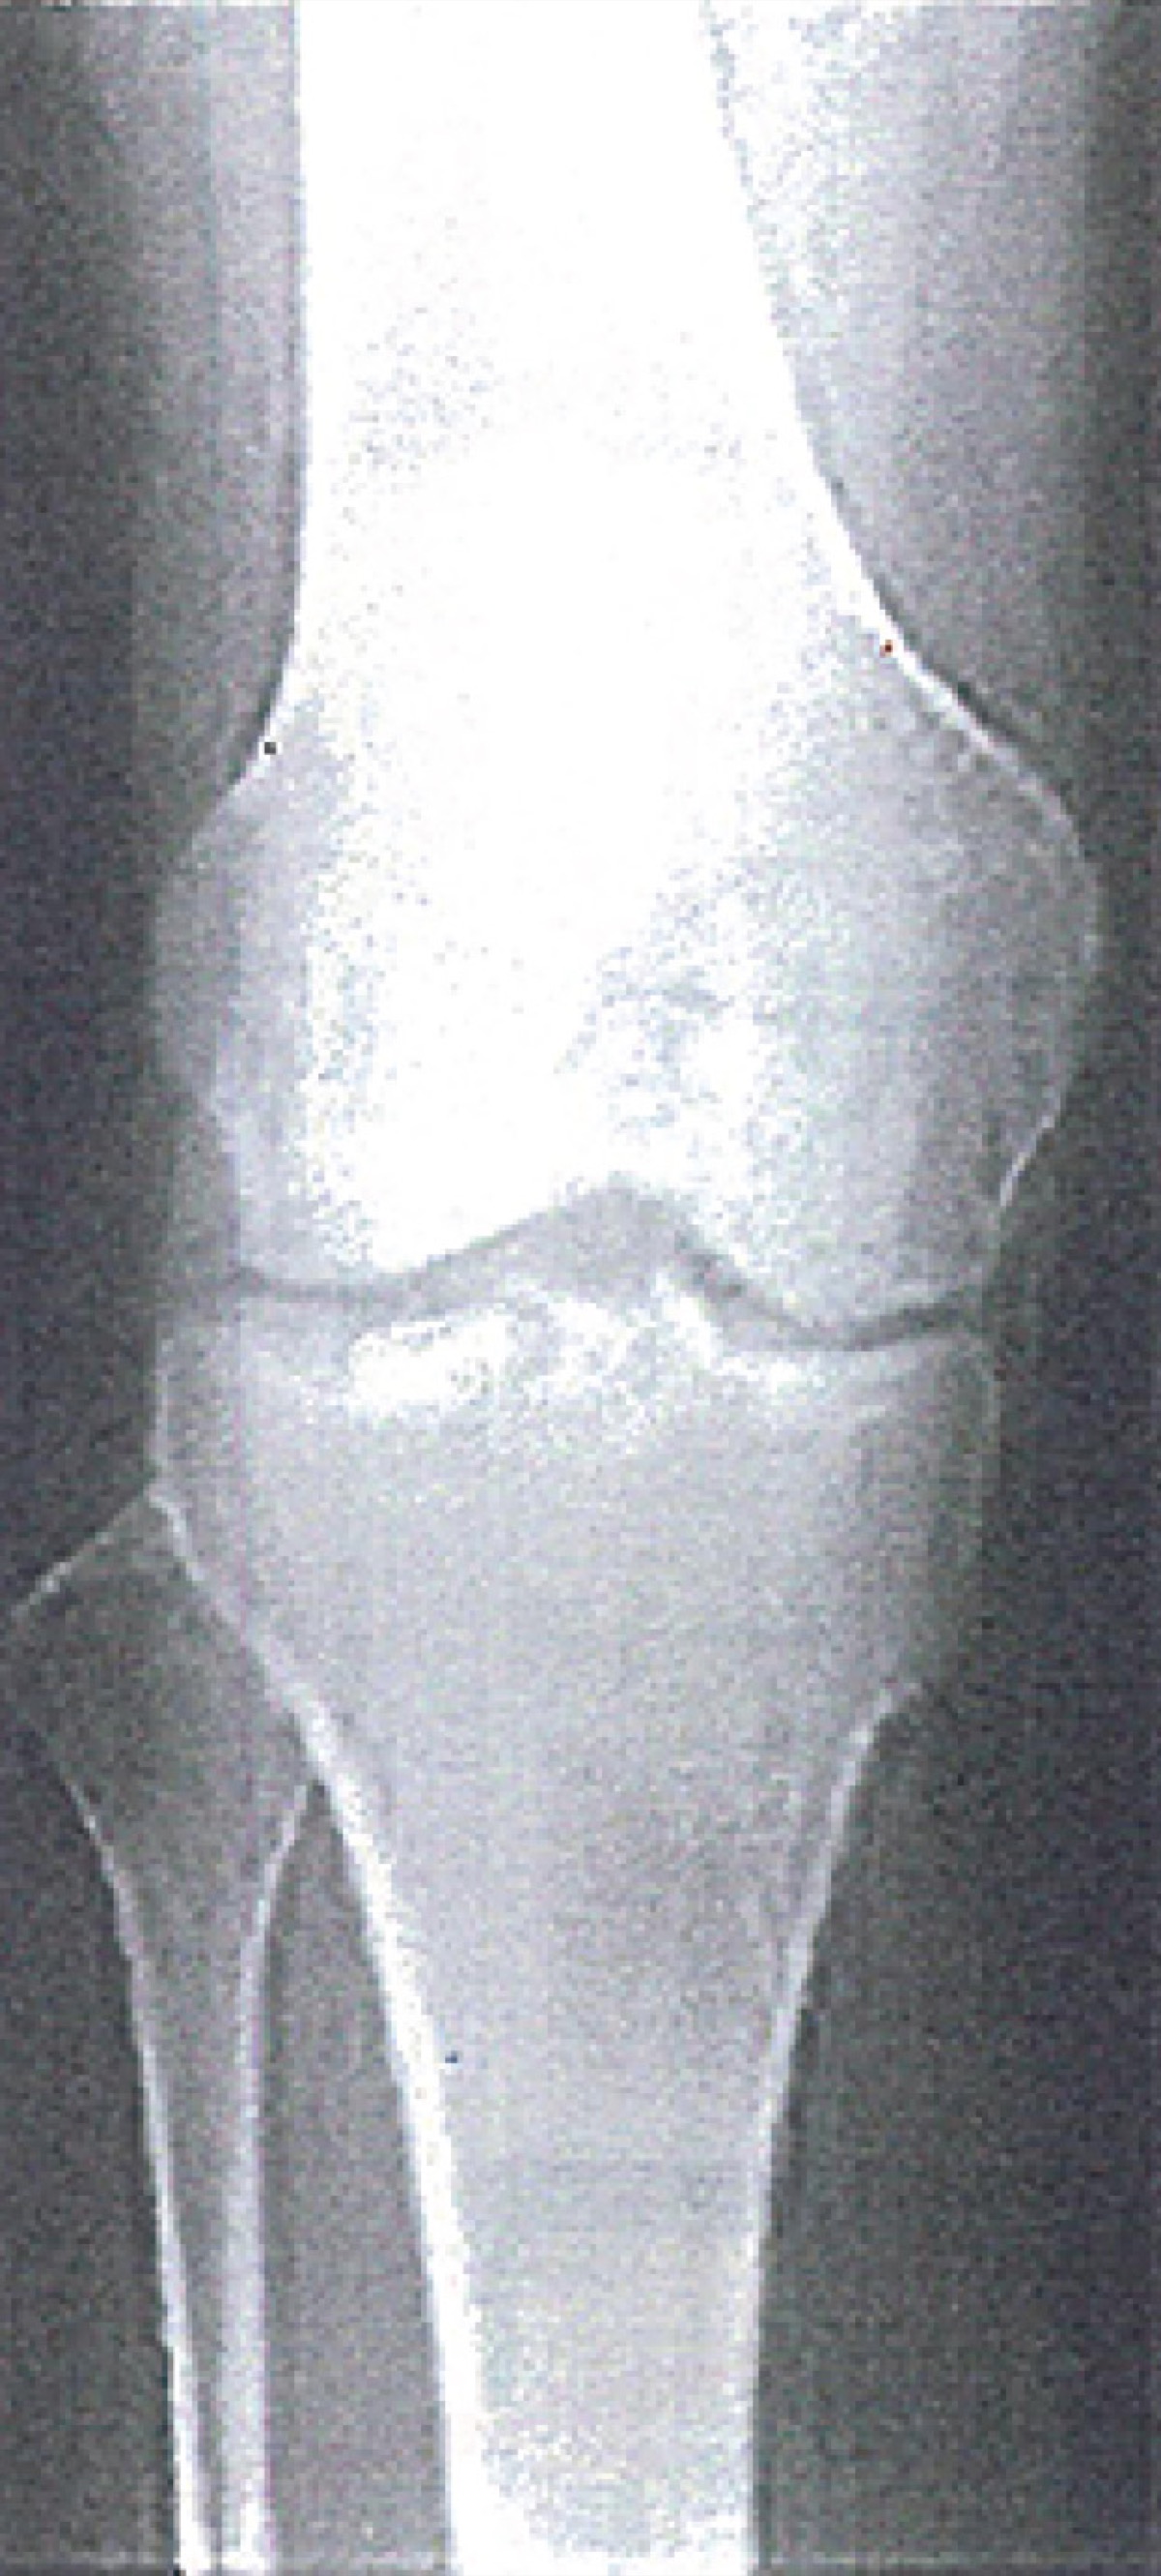

膝の痛み、自己判断は禁物

「立ち上がろうとしたら膝に痛みを感じた」「階段を降りようとしたら激痛が走った」――こうした痛みは、我慢せずに過ごしたいもの。寒川駅近くのマルヤマ接骨院に、原因などを聞いた。

「体重をこの2つの膝関節で支えているぶん、ストレスもかかります。「軟骨がすり減って痛むのか」と言われる方も多いですが、軟骨に痛覚神経はありませんし、軟骨がすり減って痛むことはないのです。高齢者の膝の痛みは軟骨から来るものではなく関節を包んでいる滑膜(かつまく)にある事が多いようです。滑膜には痛覚神経があり、その柔軟性が失われると痛みが生じます。滑膜は軟骨に栄養を与える滑液を供給したり、吸収する働きもあります。滑膜の柔軟性がなくなり、機能が低下すると滑液が吸収されにくく、結果として膝に水がたまりやすくなります」

「当院は手技などを用いて、滑膜の柔軟性を回復に導く施術を行います。滑膜が正常に戻れば溜った水も吸収されて減りやすくなります。軟骨が原因だからと高額なサプリ等を飲み続ける方もおられるかもしれませんが、自己判断は禁物です。痛みは我慢せず気軽にご相談下さい」